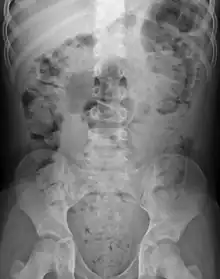

Abdominal X-rays are generally only performed if bowel obstruction is suspected, may reveal extensive impacted fecal matter in the colon, and may confirm or rule out other causes of similar symptoms.[22][15]